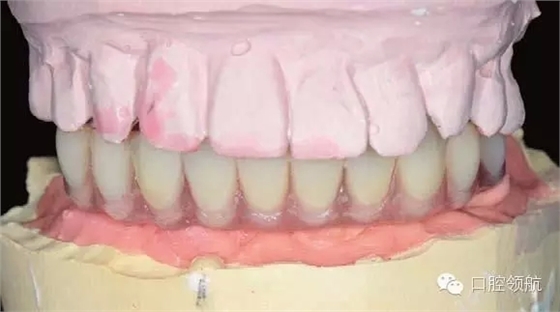

圖6-13和圖6-14分別為牙合架上的塑料過渡義齒。因為考慮縮短制作的時間,因此All-o n-4的術(shù)后螺絲固位過渡義齒使用自凝材料,同時用硅橡膠包埋蠟牙法制作。

圖6-13 排牙結(jié)束后的正面照片